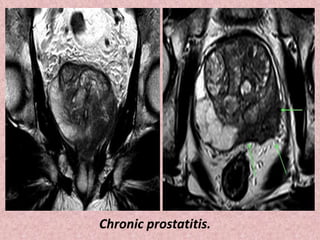

Note extensive low signal intensity (asterisks) throughout the

peripheral zone, indicative of chronic prostatitis

Chronic prostatitis.